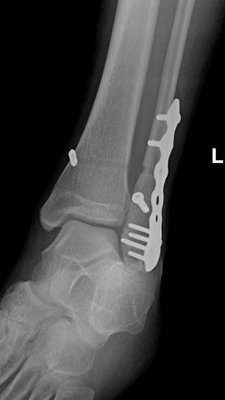

Repair of Fracture of Fibula With Wide Syndesmosis, with Plate, Screws, and Tightrope Button

A surgical procedure performed to repair fractures of one or both ankle bones. An incision is made to expose the broken bone. An additional incision is made if both bones need to be repaired. The bone fragments are then brought into alignment and fit with a metal plate and screws to keep them stable while they heal together. Some fractures can be repaired with screws alone.

Depending on the fracture location, the surgical process may differ slightly in equipment and procedure, but in general, a cut is made above the fracture site and the bones are pieced back together. Then a metal plate and screws and placed in to ensure healing in the correct manner.